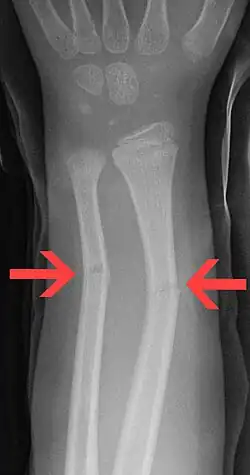

Eine Grünholzfraktur (so benannt nach dem Knickverhalten von grünem, weichem Holz) ist ein unvollständiger Knochenbruch, bei dem die umhüllende elastische Knochenhaut (Periost) erhalten bleibt oder lediglich an der Konvexseite einreißt. Es handelt sich dabei um einen Biegungsbruch.

Ein Teil des Knochens kann dabei der Krafteinwirkung durch elastische Verformung nachgeben, während ein anderer Teil (meistens der knick-außenliegende, siehe Abb.) aufgrund der größeren Dehnungsbelastung bricht, wobei sich der Knochen im Bereich zwischen gedehntem und gebrochenem Teil längs spalten kann.